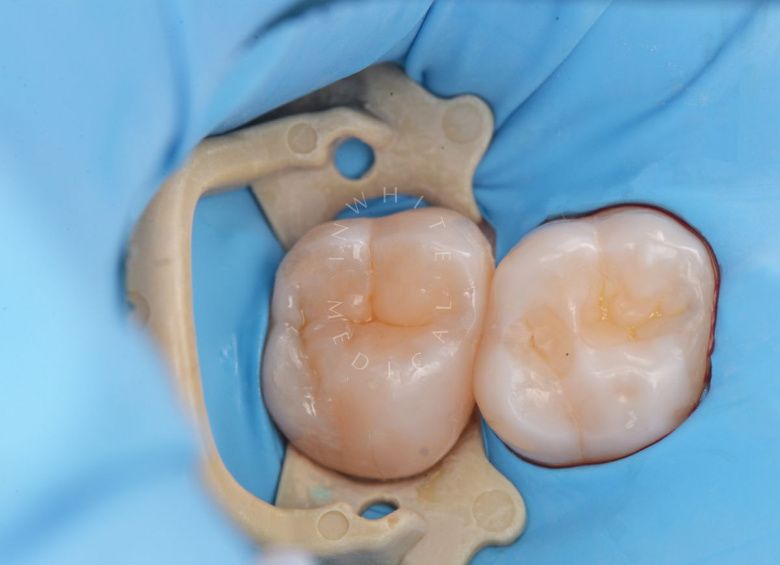

Лечение скрытого кариеса под старой пломбой

Лучшие стоматологические клиники. Лечение скрытого кариеса под старой пломбой  - после процедуры